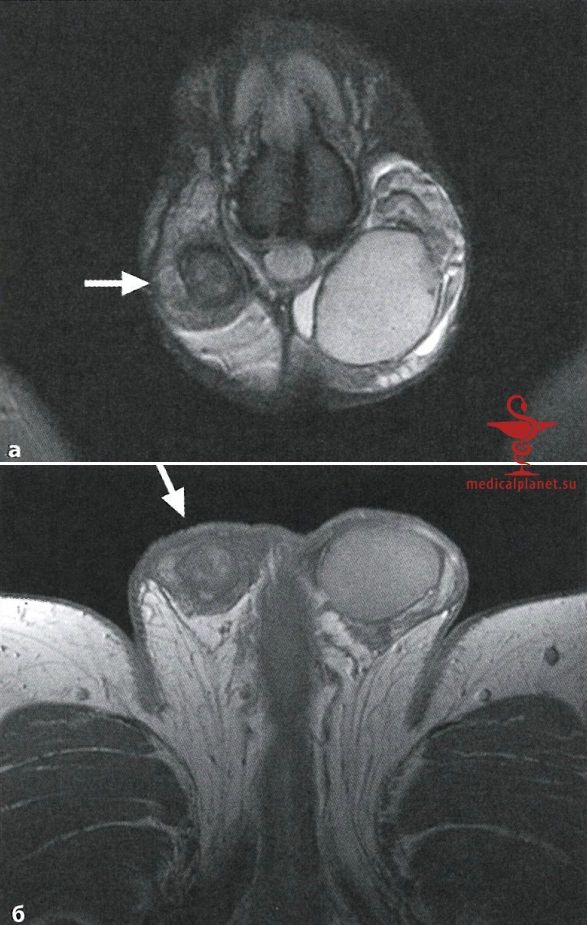

а - Т2в-ТSЕ-изображение во фронтальной плоскости. Правое яичко заметно меньше, чем здоровое левое яичко, и имеет более низкую интенсивность сигнала (стрелка).

б - Т1в-TSE-изображение в аксиальной плоскости после контрастирования. Обнаруживается только пятнистая остаточная перфузия правого яичка (стрелка) в отличие от гомогенной перфузии левого яичка.